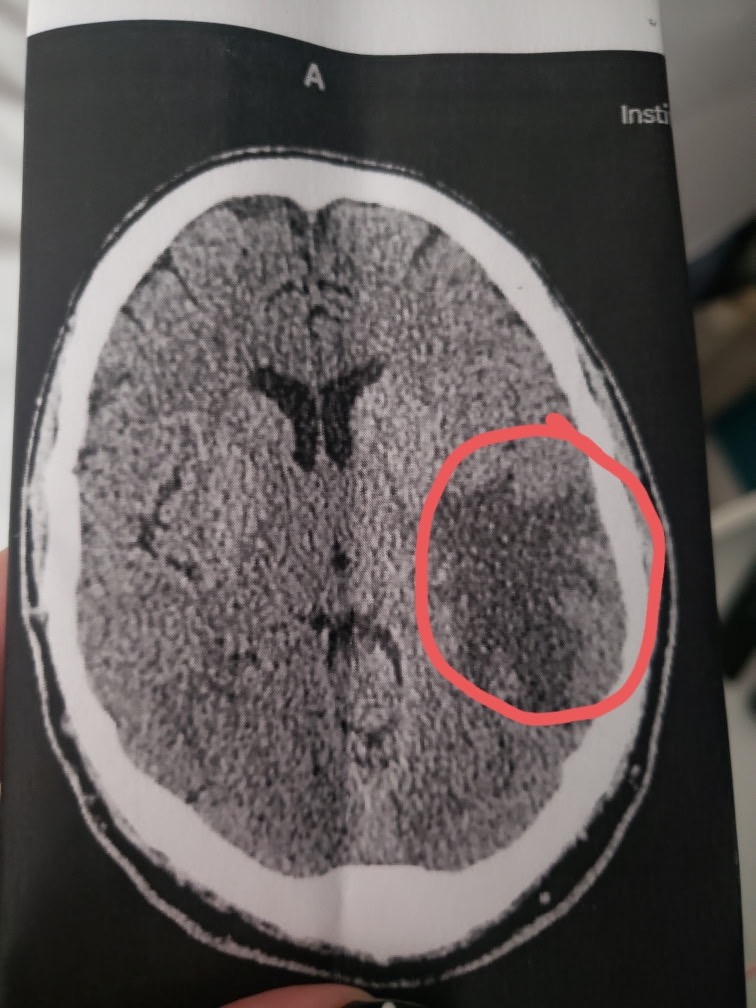

My best friend in the whole world has been diagnosed with CNS B-Cell Lymphoma. This is a rare brain cancer that requires intensive chemotherapy treatments. David is a strong guy, but he is going to need all the help he can possibly get, to get through this.